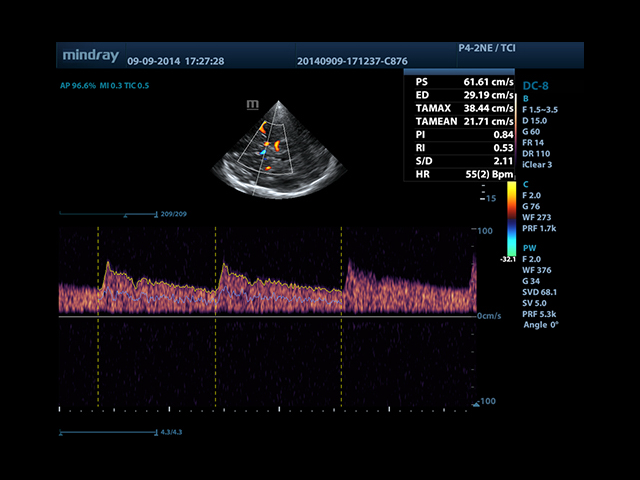

• Smart Doppler - автоматическая подстройка расположения рамки цветового доплера и контрольного объема импульсно-волнового доплера нажатием кнопки.

• Smart Doppler™ - автоматическая подстройка расположения рамки цветового допплера и контрольного объема импульсно-волнового допплера

• Автоматическая трассировка допплеровского спектра с расчетом параметров и индексов